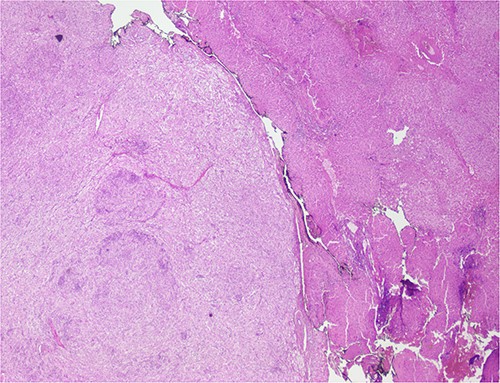

The histological evaluation of the surgical specimen revealed a storiform fusiform cell neoplasm with expansive borders, areas of a myopericytomatous pattern, and the presence of rhabdoid cells (Fig. 4). The neoplastic cells, spindled to oval, with eosinophilic and granular cytoplasm and with mild nuclear atypia, were organized in small bundles (Fig. 5). Anomalous arterial structures were observed. Neither necrosis nor mitotic figures were identified. The immunohistochemical study revealed immunoreactivity of neoplastic cells for SMA, HHF35 (Fig. 6) and HMB45 (Fig. 7), Calponin, S100 and CD31. The margins did not intersect the neoplasm. Thus, contrary to the preoperative diagnosis of hepatocellular carcinoma, the morphological aspects and the immunohistochemical profile favored the diagnosis of epithelioid angiomyolipoma.

Liver parenchyma partially occupied by a neoplastic proliferation with expansive borders.

The neoplastic cells are organized in small bundles. The cells are spindled to oval, with eosinophilic and granular cytoplasm and with mild nuclear atypia.